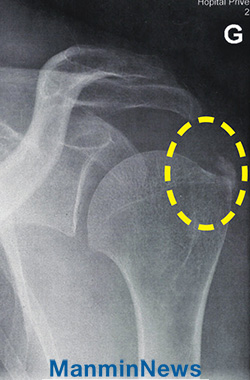

2017³â 2¿ù 20ÀÏ, Àú´Â ¾÷¹« Áß °©Àڱ⠿ÞÂÊ ÆÈ¿¡ ½ÉÇÑ ÅëÁõÀ» ´À²¼½À´Ï´Ù. ±Í°¡ÇÒ ¶§´Â ±Ø½ÉÇÑ ÅëÁõÀ¸·Î ÀÎÇØ ¿À¸¥¼ÕÀ¸·Î¸¸ ¿îÀüÀ» ÇØ¾ß ÇÒ Á¤µµ¿´Áö¿ä. Àú³áÀÌ µÇ¾î¼´Â ¾Æ¿¹ ²Ä¦ÇÒ ¼ö ¾ø¾ú°í ¿Þ¼ÕÀ» ÀüÇô ¿òÁ÷ÀÏ ¼ö ¾ø¾ú½À´Ï´Ù.

º´¿ø¿¡¼ Áø´ÜÇÑ °á°ú, ¾î±ú°üÀý¿¡ ¼®È¸°¡ Ä§ÂøµÈ °ÍÀÌ ¿øÀÎÀ̾ú½À´Ï´Ù. ÀÇ»ç´Â ÃßÀ̸¦ ÁöÄѺ¸¸ç ¸î ÁÖ ÈÄ¿¡ ÃÊÀ½ÆÄ »çÁøÀ» Âï¾îº¸ÀÚ°í ÇÏ¿´½À´Ï´Ù. ±×¶§ °¡¼µµ Áõ»ó°ú ÅëÁõÀÌ ±×´ë·Î ³ªÅ¸³ª¸é ¼ö¼úÀ» ÇØ¾ß ÇÑ´Ù°í ÇÏ¿´Áö¿ä. ÇÏÁö¸¸ Àú´Â Á¤È®ÇÑ º´¸íÀ» ¾Ë¾Ò±â¿¡ »ì¾Æ °è½Å Çϳª´Ô²² Ä¡·á¹Þ°í ½Í¾ú½À´Ï´Ù.

X-ray ÃÔ¿µ °á°ú, ÁÂÃø °ß°üÀý¿¡ ¼®È¸ Ä§Âø ¼Ò°ßÀÌ º¸¿´À¸³ª ¼º·ÉÀÇ ºÒ¼¼·Ê¸¦ ¹ÞÀº ÈÄ ÅëÁõÀÌ »ç¶óÁö°í ÀÚÀ¯ÀÚÀç·Î ¿òÁ÷ÀÏ ¼ö ÀÖ°Ô µÊ.